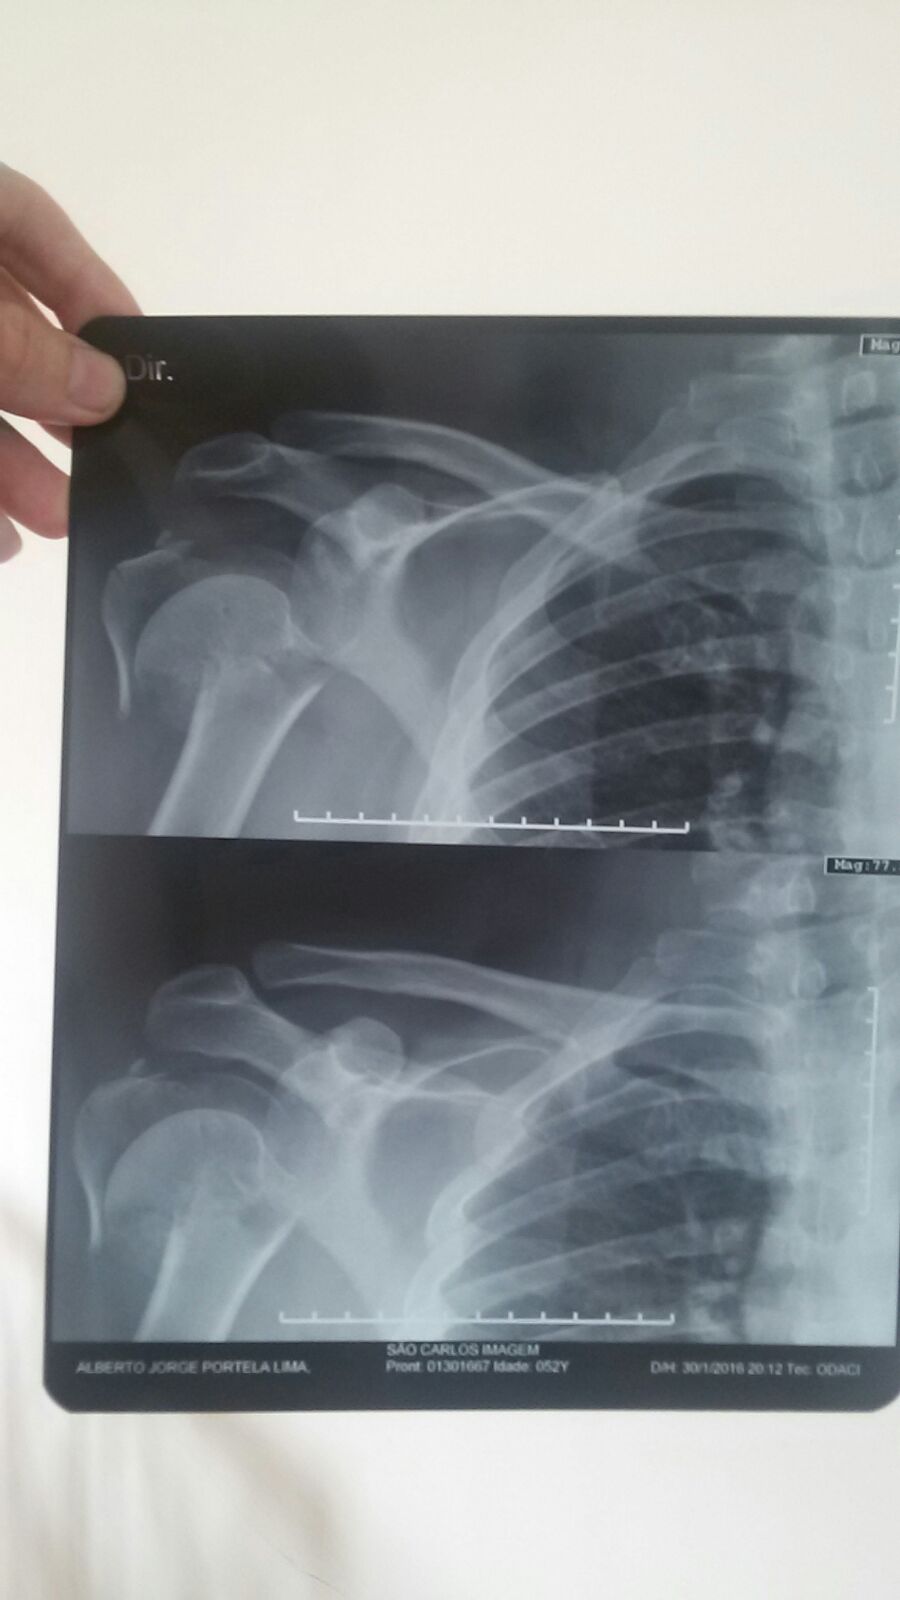

Bebeto, como é mais conhecido no meio motociclístico, não teve apenas escoriações leves. Além dos danos à moto que podem evoluir para ‘perda total’, Bebeto teve fratura do úmero o que exigiu a colocada de uma prótese que custou R$ 42.000,00, fora todas as outras despesas.

GALERIA DAS LESÕES – Clique na foto para visualizar

E vamos as contas do prejuízo do Bebeto. A sua Harley-Davidson 883 para ser recuperada custará a bagatela de R$ 22.000,00 reais – quase perda total. As contas de hospital começam em R$ 42.000,00 com a prótese e devem crescer com os custos de cirurgia e internação. Teremos ainda os remédios e a fisioterapia e os 15 dias que o Bebeto ficou parado por conta da cirurgia e ainda serão necessários mais de seis meses até a total recuperação e seu pronto restabelecimento para que possa voltar a pilotar sua motocicleta. Enfim, podemos afirmar que esta conta direta seria algo em torno de R$ 200.000,00 e a parte indireta que seria não poder curtir sua moto, não poder realizar tarefas normais comuns para quem não tem prótese no braço e o prejuízo aos cofres do Estado do Ceará por ter afastado um competente assessor parlamentar, não tem preço.